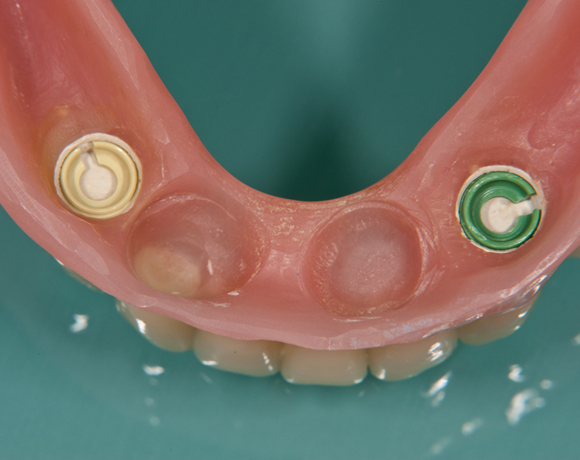

Bild 07: Die leeren Matritzengehäuse

Bild 08: Mit neuen Retensionseinsätzen versehen